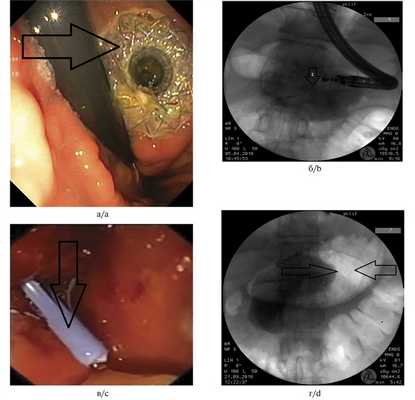

3. Электрокоагуляция тканей желудка и стенки кисты с последующей цистотомией стенки кисты посредством 8,5 Ch цистотома (MTWEndoscopieManufaktur, Germany) (рис. 2). Рис. 2. Цистотомия стенки кисты устройством МТW (MTW Endoscopie Manufaktur, Германия) (случай 1).

5. Установка трехлепесткового стента MTW таким образом, чтобы конец, содержащий два лепестка, оставался в просвете кисты (рис. 3, 4). Рис. 4. Эндоскопическая цистогастростомия с установкой в кисту трехлепесткового стента MTWE. Рис. 3. Эндоультразвуковое сканирование псевдокисты поджелудочной железы после цистотомии (в просвете определяется катетер) (пациент 1).

Пластиковые стенты применяли при наличии «зрелой» фиброзной капсулы толщиной от 3 до 9 мм и однородном содержимом кисты. Металлические саморасширяющиеся стенты устанавливали в отсутствие капсулы, при инфицированном содержимом и наличии секвестров (рис. 2). Рис. 2. Состояние после цистогастростомии. а — саморасширяющийся стент в просвете инфицированной кисты указан стрелкой (изображение получено при эндоскопической ультрасонографии); б — саморасширяющийся стент в просвете инфицированной кисты указан стрелкой 2 (по данным рентгенографии); в — пластиковый стент в просвете неинфицированной кисты указан стрелкой (изображение получено при эндоскопической ультрасонографии); г — пластиковый стент в просвете неинфицированной кисты указан стрелками (по данным рентгенографии). a — self-expanding stent inside infected cyst is indicated by the arrow 2 (us); b — self-expanding stent inside infected cyst is indicated by the arrow 2 (X-ray); c — plastic stent inside sterile cyst is indicated by the arrow (us); d — plastic stent inside sterile cyst is indicated by the arrows (X-ray).